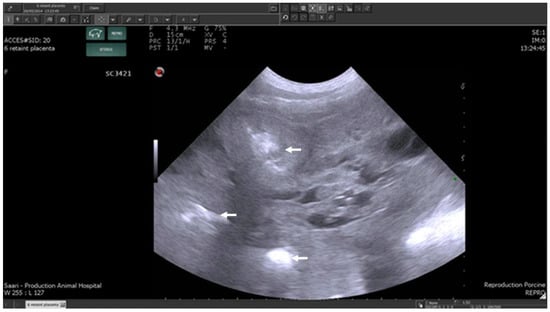

3.1.2. The Puerperal Uterus

4.4. Problems with Non-Puerperal Vulval Discharge